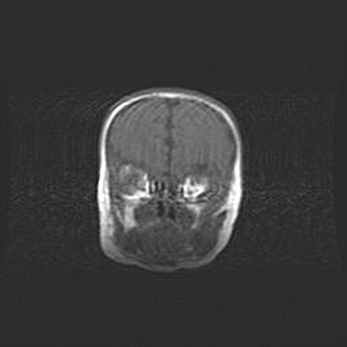

Множественные кисты обоих полушарий головного мозга, наибольшая из них в правой затылочной области. Ассиметричная атрофическая гидроцефалия.

Возраст: 7 месяцев

Вес: 5660 г

Пол: мужской

Окружность головы: 41,5 см

Срок гестации: 28-29 недель

Кисты головного мозга развиваются в результате многоочаговых некрозов вещества мозга и возникают вследствие перенесенной перинатальной инфекции, менингитов, энцефалитов, асфиксии, родовой травмы, расстройств мозгового кровообращения различного генеза. Образованию кист в веществе головного мозга плодов и новорожденных способствуют такие факторы, как высокое содержание в нем воды, недостаточная (или отсутствие) миелинизация и слабая астроглиальная реакция на повреждение.

Кисты могут сочетаться с гидроцефалией и другими поражениями головного мозга.